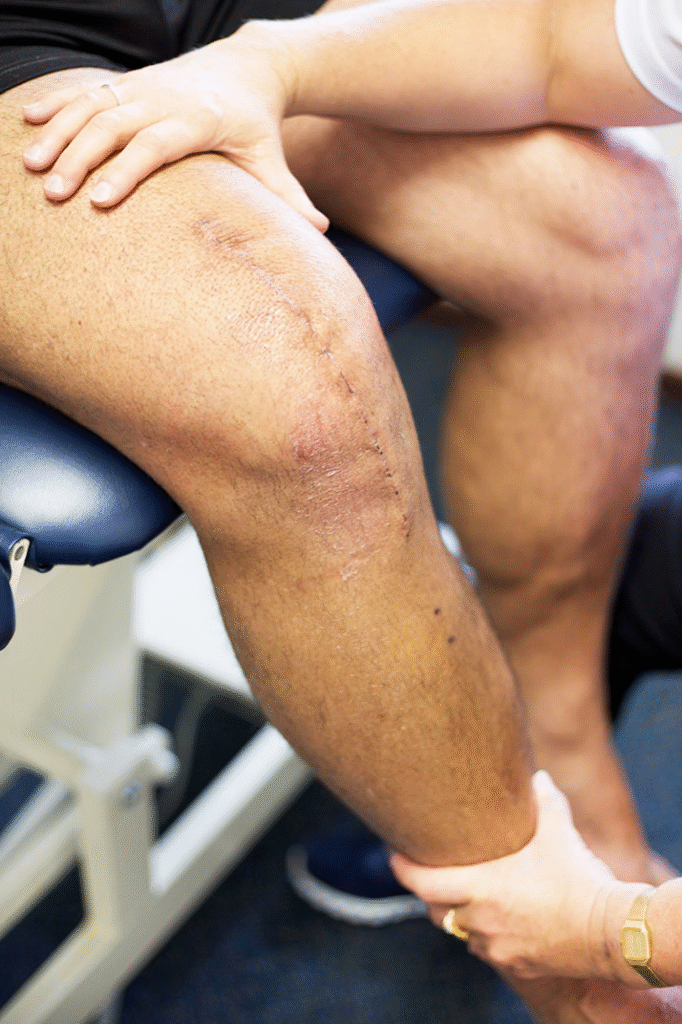

⭐ What to Expect During Recovery

Hospital Stay

- 2–3 days

Walking typically begins within 24 hours

Physiotherapy starts early to restore movement and strength